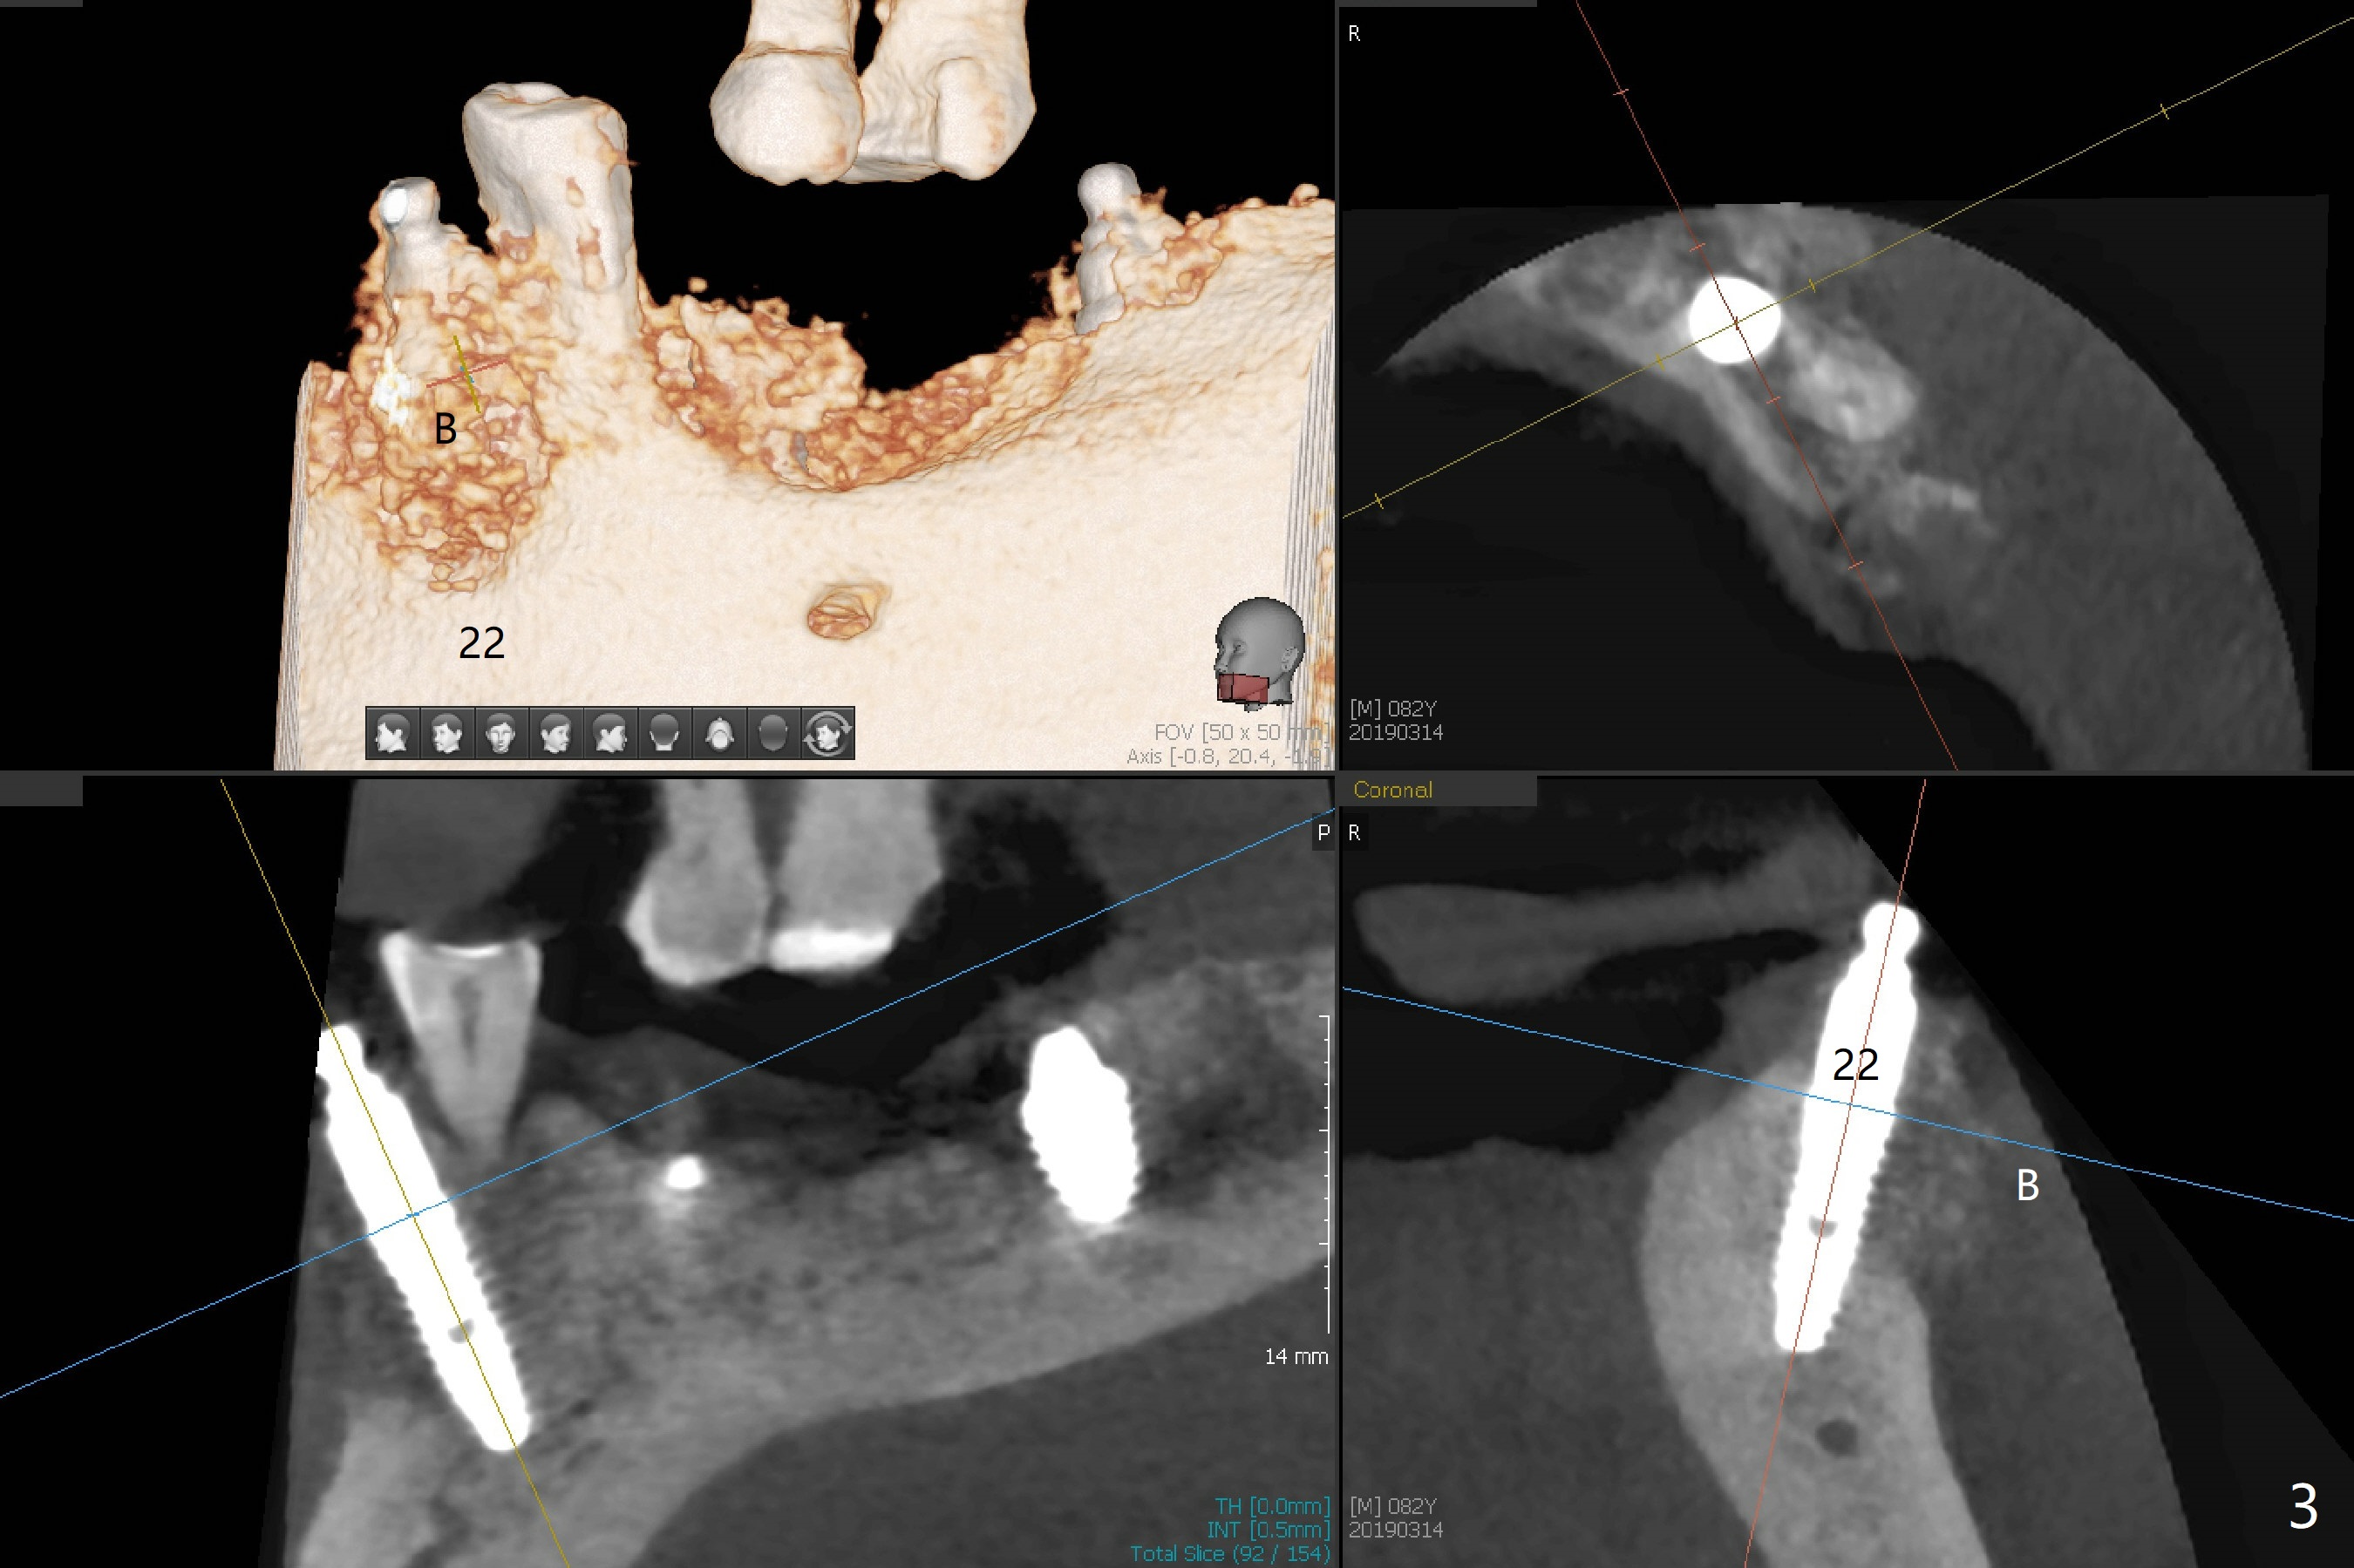

Three months post socket preservation (with buccal plate loss previously), a 3.5x11.5 mm implant is placed at #27 subcrestal (Fig.1). When implants are placed at #22 and 20 (Fig.2,4), threads are exposed buccal (B). Mixture of autogenous bone and allograft is placed to cover the exposed threads (Fig.3,5) following deep placement at #20. For safety, the implant at #20 is buried. Pain control at #18 is poor when initial osteotomy is being established (Fig.6 *), as related to severe infection. Repeated block anesthesia allows to finish implant placement with primary stability; a 3.5x2 mm ball abutment is placed (Fig.7). With placement of 2 other ball abutments at #27 and 22 (Fig.3), the lower existing RPD is converted to a removable provisional (Fig.8). With addition of acrylic, the socket of #20 is covered (Fig.9). There is no apparent bone #20 distal 3 months postop (Fig.10,11 <). Re-graft is needed? The implant at #21 appears immediately subgingival 5 months postop (Fig.12 *). The distobuccal threads are exposed (Fig.13). After decortication, allograft is placed, followed by 6-month membrane. In fact, a shorter and smaller implant should be placed instead. The patient has to wear the RPD for mastication. It would be more painful without it. Later the tissue surface of the RPD is trimmed.